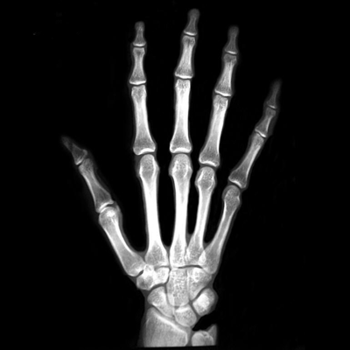

7.2. Real X-ray images

After testing our proposed method on several synthetic images, we now consider applying it on real medical images. Here, we consider a hand X-ray image as the source image (Fig. 7(a)) and a deformed hand X-ray image as the target image (Fig. 7(b)). Fig. 7(c) shows the original absolute intensity difference between the two images. It can be observed that different fingers are displaced in a nonuniform manner (for example, the displacement of the index finger is much larger than that of the little finger), while the wrist remains almost the same. Therefore, a simple rigid transformation is insufficient for yielding a good registration. As shown in Fig. 7(d), our proposed method successfully deforms the source image to match the target image, and the final intensity difference is significantly smaller (see Fig. 7(e)). From the deformed underlying grid in Fig. 7(f), it can be observed that the mapping is smooth and bijective. For comparison, both LDDMM [5] and DDemons [47] fail to register the fingers and are non-bijective (see Fig. 7(g), Fig. 7(h), and Fig. 7(i)).

We then consider another example of registering two hand X-ray images with larger deformations (see Fig. 8(a) for the source image, Fig. 8(b) for the target image, and Fig. 8(c) for their absolute intensity difference). The warped image produced by our proposed method (Fig. 8(d)) again closely resembles the target image with the intensity difference significantly reduced (see Fig. 8(e)). Fig. 8(f) shows that the mapping is smooth and bijective. For comparison, note that LDDMM [5] fails to match the fingers (Fig. 8(g)). While DROP [18] is capable of registering the fingers (Fig. 8(h)), it distorts the boundary shape of the overall image (Fig. 8(i)).